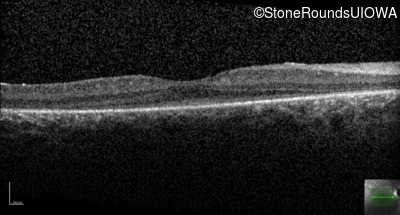

Age at visit: 15 years

This 15 year old male has had very poor vision and nystagmus since the first year of life.

Age at visit: 12 years

Age at visit: 13 years